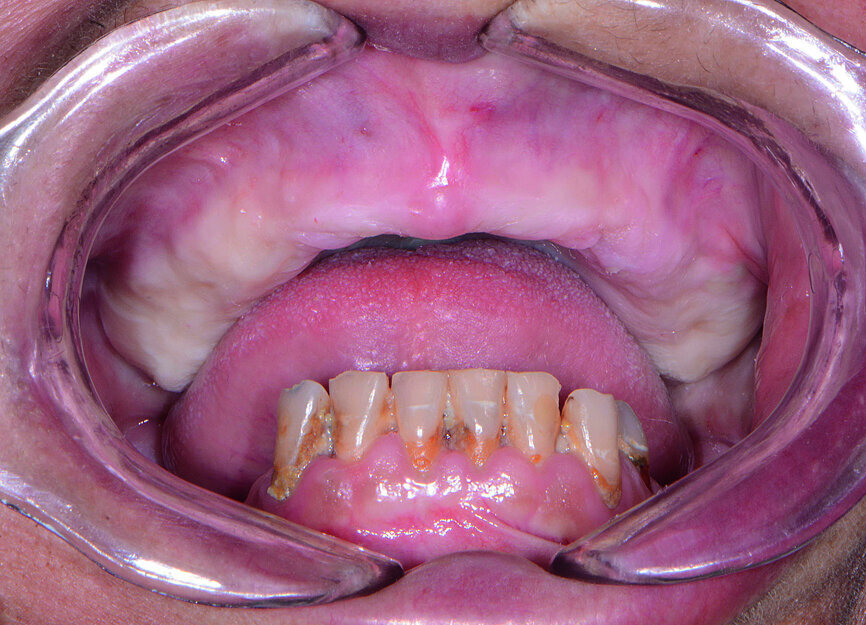

Fig. 1: Pre-op retracted view.

Fig. 2: Pre-op retracted view without denture.

A female patient in her mid-fifties presented for treatment with an edentulous maxilla and grossly decayed, hyper-erupted mandibular dentition (Figs. 1 & 2). The patient was a heavy smoker, had not seen a dentist in several years, and was not taking proper care of her remaining teeth owing to pain and discomfort. The patient’s maxillary denture had become increasingly loose-fitting since losing her teeth nearly a decade prior. Her desire for a restoration that felt and functioned more like natural teeth led her to my practice, where she could undergo the surgical and prosthetic phases of treatment under one roof. Intra-oral and radiographic evaluation indicated sufficient bone volume for full-arch implant therapy.